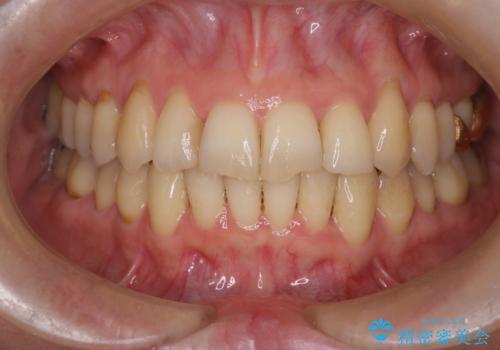

患者様にしっかりとインビザラインを使用して頂けたことで綺麗な仕上がりとなりました。